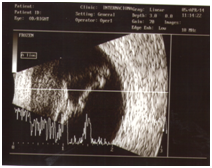

This is a case of 24 years old boy who presented to us due to rapidly progressive deterioration of vision in both eyes over a period of 3 months. His past medical history included a diagnosis of Tourette syndrome (TS) and depression since the age of 14 years. He was not compliant to his medical therapy for fast 1 year. His mother noticed that he was confined to his room for past few days and was stumbling upon the objects at home. She described his motor tics as having blepharospasm, clapping, gouging his fingers into his eyes, and punching himself in the periorbital area. She decided to seek ophthalmologist opinion when she noticed exacerbation in the tic frequency and severe periorbital ecchymosis over the right eye. During the examination, patient was well oriented, did not show any vocal or motor tics and no signs of cognitive impairment. On ocular examination, there was periorbital ecchymosis in the right eye and multiple mechanical scratch marks in the periorbital region laterally and also on face (Figure 1). The nature of the external injuries was commensurate with a tendency of motor tics described by his mother. Ocular movements were full and free. Visual acuity was no perception of light in the right eye and hand movement close to face in the left eye. Slit lamp biomicroscopy showed clear cornea in both eyes (Figure 2). Right eye examination revealed posterior synechiae with near total cataract. There was evidence of KPs, mild aqueous cell and posterior sub capsular cataract in the left eye. Even though the fundus visibility was limited by vitreous hemorrhage, a total retinal detachment with proliferative vitreoretinopathy could be seen in his both eyes (Figure 3). Echography revealed a closed funnel retinal detachment in both eyes (Figure 4).

Figure 4 Echo scan from the patient.